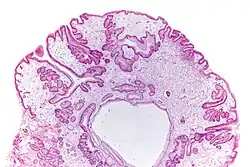

Micrograph of a gastric juvenile polyp, as may be seen in juvenile polyposis syndrome. H&E stain